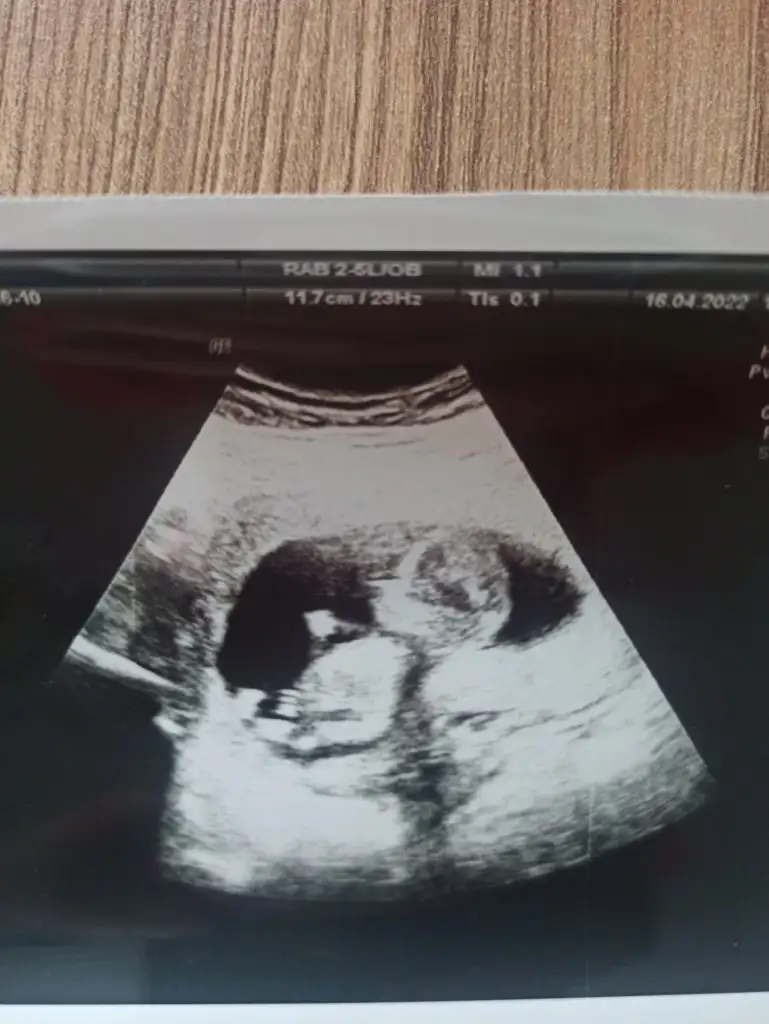

tahmın alabilir miyim karından ultrason 10+2🌸❤️